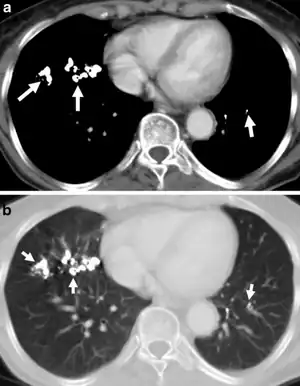

Barium has a high radio-opacity and the disease may develop after few months of exposure. Extremely dense, discrete small opacities of 2–4 mm diameter, sometimes of a star-like configuration, are seen on the radiograph. Their distribution is uniform. When they are very numerous, superimposition may give the impression of confluency, but this does not seem to occur in reality. The hilar lymph nodes can be very opaque but not enlarged. After cessation of exposure, there is a gradual clearing of the opacities.

The barium particles can be seen as opaque shadows on the chest X-rays of people with baritosis. However, being a benign condition, it neither interferes with lung function nor causes symptoms other than a mild cough.

After exposure to barium dust ceases, the X-ray abnormalities gradually resolve.[1]